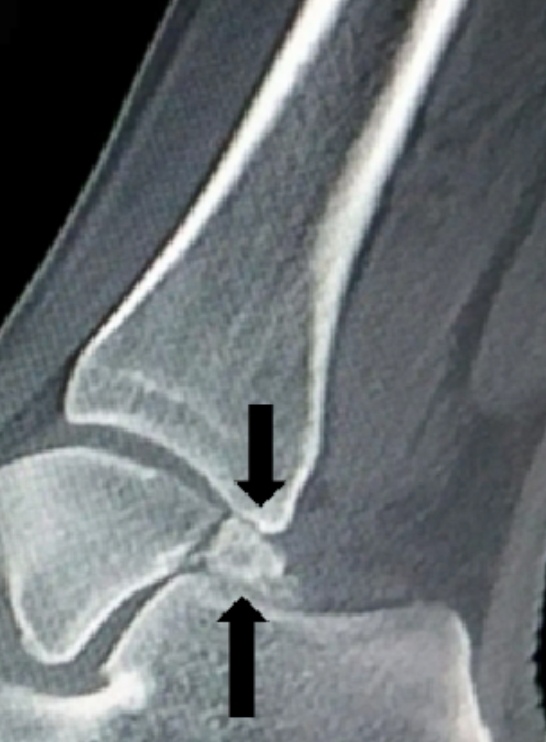

其二,副骨形成的部位狭小,在活动过程中与邻近骨或肌腱软组织之间的摩擦、撞击、挤压,导致滑囊炎和肌腱炎,引起疼痛。如距骨后三角骨在踮起脚尖动作下会被上方的胫骨与下方的跟骨挤压,就如夹核桃一样(如下图),产生疼痛,这种情况多见于运动员、芭蕾舞者。